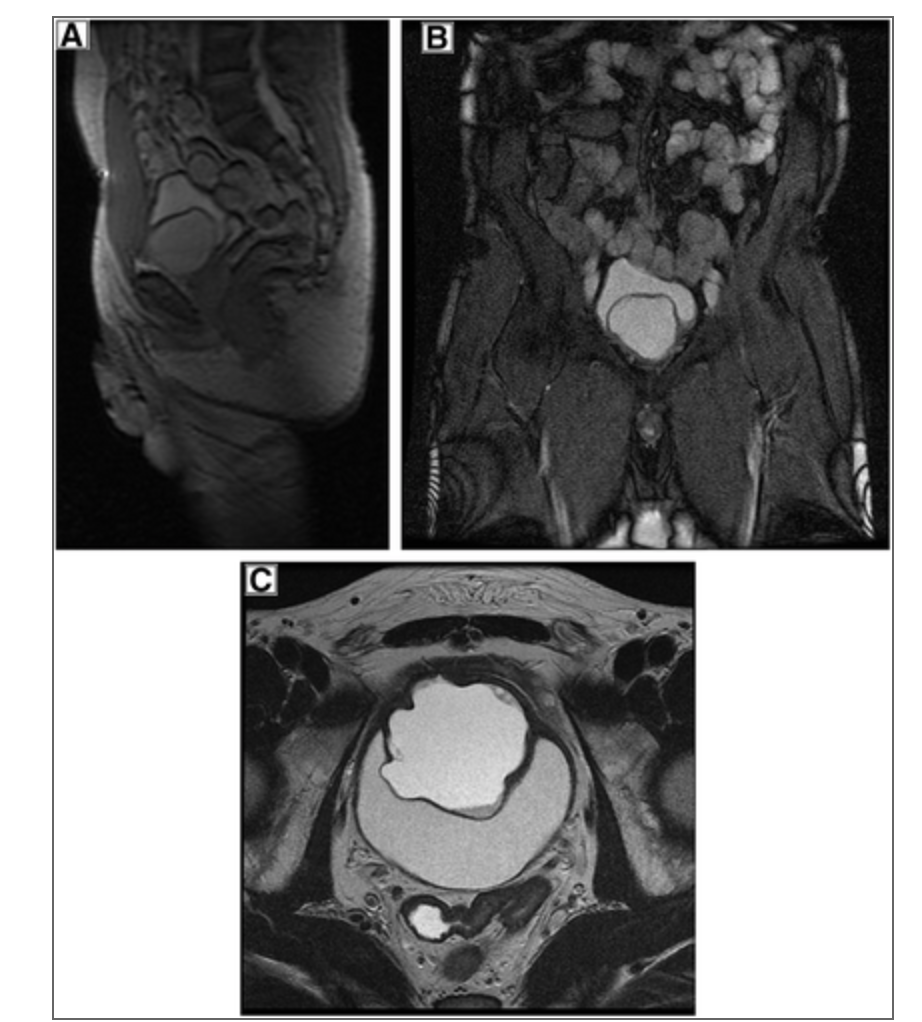

Lymphocele with pressure effect on Tx Kidney

What are 4 causes of this condition?